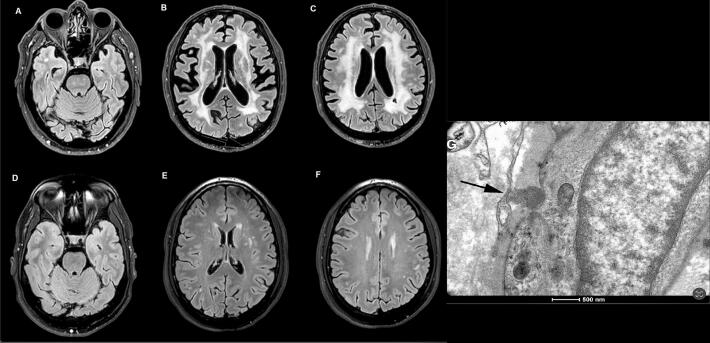

CADASIL(大脑常染色体显性动脉病变伴皮质下梗死和脑白质病)是一种由NOTCH3基因突变引起的遗传性小血管疾病,以复发性中风、认知能力下降和精神症状为特征。本报告提出了一种新颖的NOTCH3 c.1564t>a (p.Cys522Ser)突变与早发性帕金森病和显著白质病变相关。我们描述了一位表现为早发性帕金森病的患者,其特征是运动迟缓和僵硬,同时通过神经影像学观察到广泛的白质病变。基因检测发现了一种新的c.1564NOTCH3基因中的T > A (p.Cys522Ser)突变,有助于CADASIL的临床诊断。该病例强调了CADASIL的表型变异性和非典型表现的可能性,包括帕金森病。基因突变的早期识别有助于对受影响的个人及其家庭进行适当的管理和咨询。NOTCH3突变与帕金森病之间的关联机制有待进一步研究。我们的研究结果有助于理解CADASIL,建议临床医生在早发性帕金森病的鉴别诊断中考虑CADASIL,特别是在并发白质病变的患者中。

CADASIL (Cerebral Autosomal Dominant Arteriopathy with Subcortical Infarcts and Leukoencephalopathy) is a hereditary small vessel disease caused by mutations in the NOTCH3 gene, characterized by recurrent strokes, cognitive decline, and psychiatric symptoms. This report presents a novel NOTCH3 c.1564 T > A (p.Cys522Ser) mutation associated with early-onset parkinsonism and significant white matter lesions. We describe a patient who presented with early-onset parkinsonism, characterized by bradykinesia and rigidity, alongside extensive white matter lesions observed through neuroimaging. Genetic testing revealed a novel c.1564 T > A (p.Cys522Ser) mutation in the NOTCH3 gene, contributing to the clinical diagnosis of CADASIL. This case underscores the phenotypic variability of CADASIL and the potential for atypical presentations, including parkinsonism. Early identification of genetic mutations can facilitate appropriate management and counseling for affected individuals and their families. Further research is warranted to explore the mechanisms underlying the association between NOTCH3 mutations and parkinsonism. Our findings contribute to the understanding of CADASIL, suggesting that clinicians should consider CADASIL in differential diagnoses of early-onset parkinsonism, especially in patients with concurrent white matter lesions.